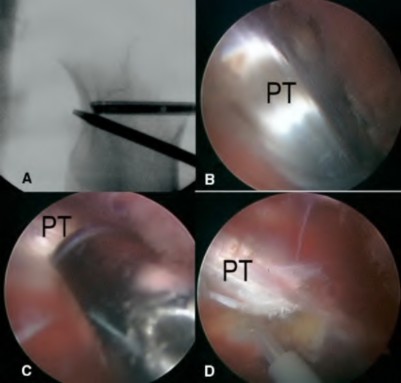

A 67-year-old diabetic male presents 4 months status post right total knee arthroplasty (TKA) complaining of pain and stiffness for the last four weeks. A clinical photograph is shown in Figure A. Radiographs and a bone scan are shown in Figures B, C and D. Blood work shows an ESR of 14mm/hr (normal 0-12mm/hr) and a CRP of 2mg/L (normal 1-3mg/L). Knee aspiration yields WBC of 1000, 30% PMNs, and a negative gram stain. He finished a 14-day course of antibiotics prescribed to him by his primary care physician one week ago. Which of the following is the most appropriate next step in management?

Figure A is a clinical photograph demonstrating a swollen, erythematous right knee with a well-healed incision from a previous TKA. Figure B and C are AP and lateral radiographs of the right knee with no obvious acute findings. Figure D is a bone scan demonstrating increased uptake in the post-operative knee, which is consistent with the 4 month follow-up.